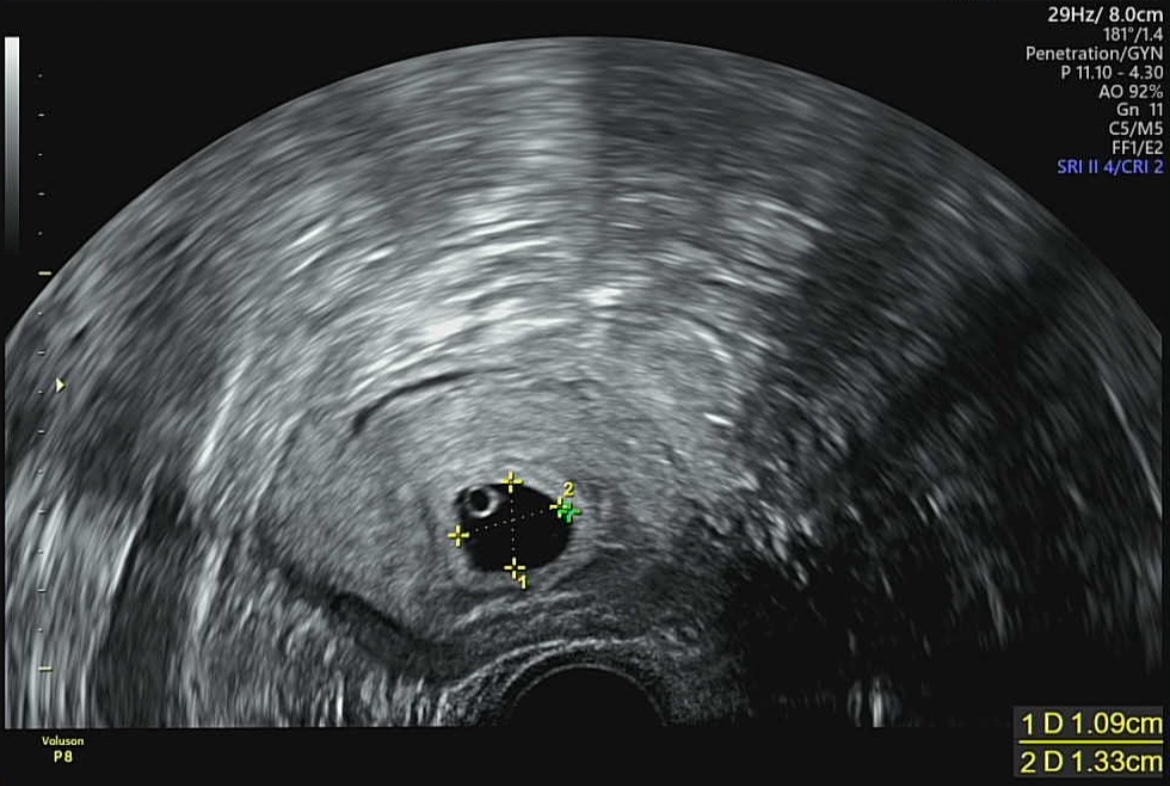

초음파상으로 확인 되는 형태는 하얀 자궁속에 까만 동그라미가 아기집이며, 그 아기집 안에 동그란 반지모양의 하얀색 텅 빈 동그라미가 난황입니다. 난황은 태아가 탯줄을 통해 영양이 공급되기 전까지 임신초기의 태아에게 영양을 공급해주는 것을 난황이라고 합니다. 저희 산부인과 의사선생님은 간단하게 아기밥이라고 표현하였습니다.

일반적으로 난황은 일반적으로 아기집을 처음 보게되는 5주차보다 한 주정도 더 지난 6주차에 확인가능하다고 합니다. 이 시기의 태아는 1mm~2.5mm이기 때문에 난황의 동그라미 반지 옆에 점처럼 있어서 이 시기에는 너무 작아서 눈으로 확인하기 어렵다고 합니다.

참고로 저의경우, 네이버주수계산기로 계산했을 때 (마지막 생리 시작일 기준) 7주가 넘는 상황에 임신 사실을 알게되었습니다. 저는 주기가 긴 편이었고 네이버로만 확인했을 때에는 7주가 한참넘은 상황이었지만, 처음 초음파로 확인할 당시 아기집과 난황을 함께 확인할 수 있었습니다.(5주6일)